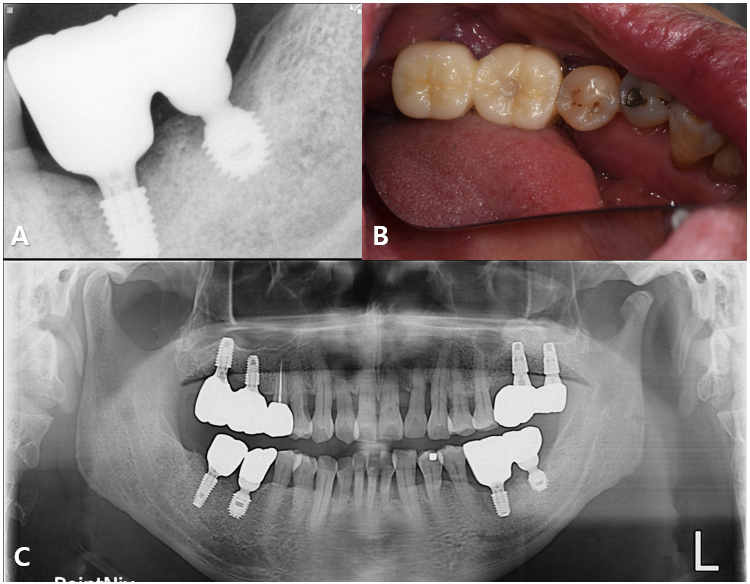

After 2.5 years, the prosthesis remained functional without significant complications, and radiographs confirmed stable peri-implant bone levels surrounding both fixtures (Fig. 6).

An appropriate stock abutment for fixture (#35) was procured, enabling reuse of the existing implant for patient comfort and reduced surgical morbidity. The restoration was completed based on the information provided by the implant finder service (Fig. 8A and 8B).

At the 6 year follow-up, the implants on the mandibular left side remained functional and stable. However, the patient experienced implant fracture in the maxillary right quadrant, possibly due related parafunctional activity such as bruxism (Fig. 8C).8